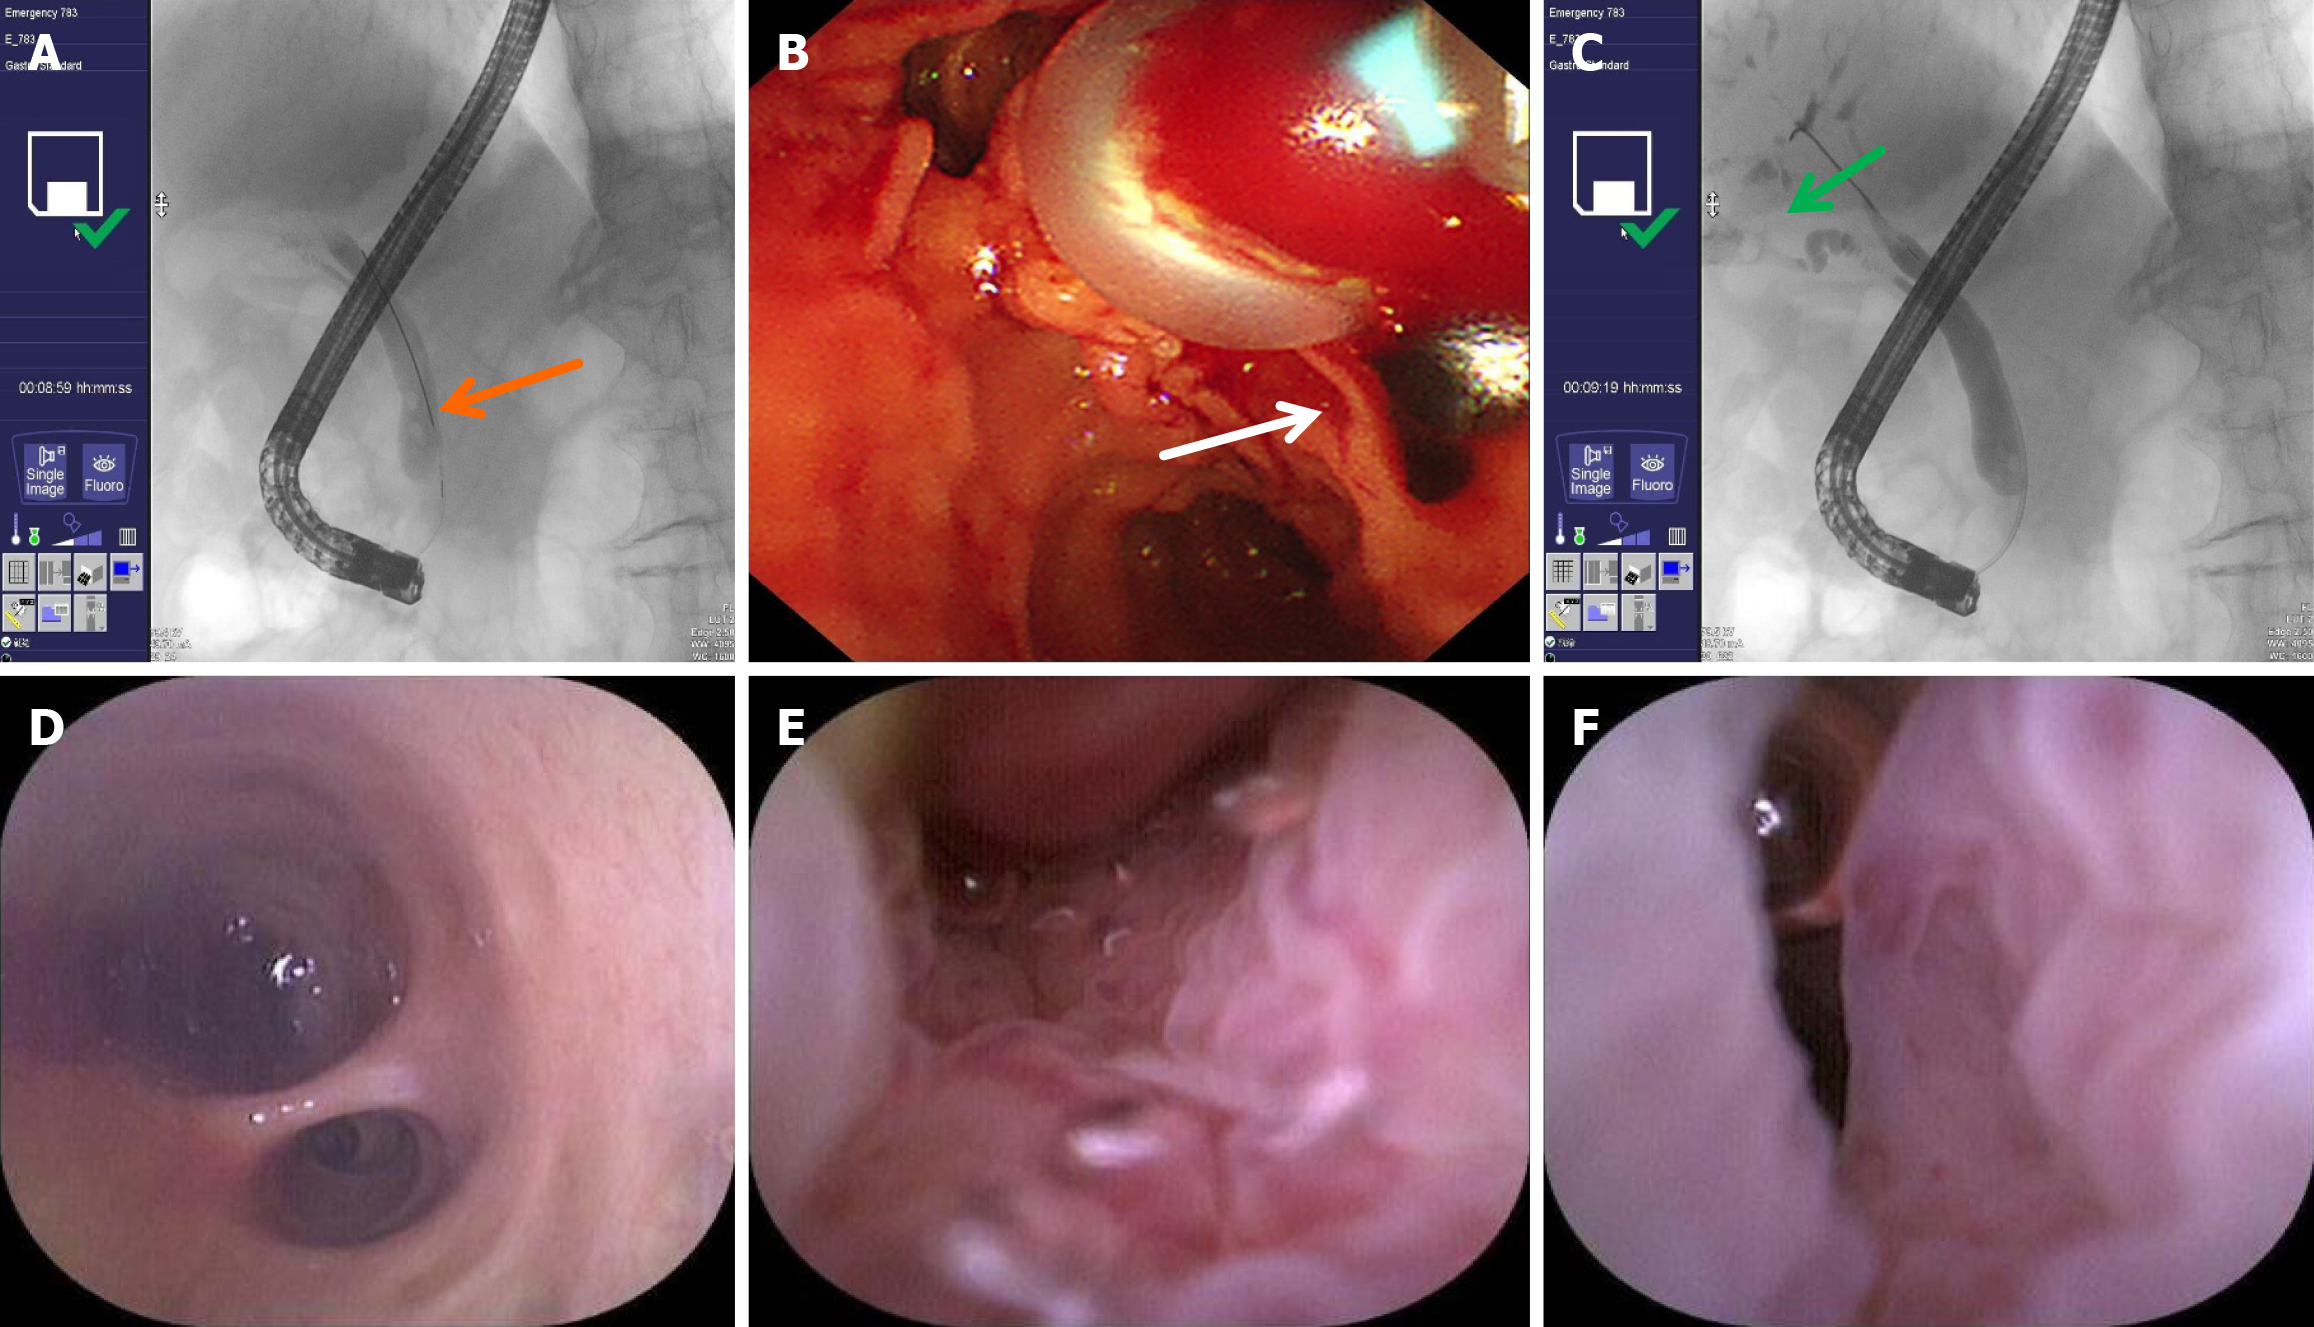

Figure 4 endoscopic retrograde cholangiopancreatography performed on September 19, 2024.

A: Common bile duct stones on cholangiography (orange arrow); B: Stones extracted with balloon (white arrow); C: Poor visualization of the bile duct at the hepatic portal region on cholangiography (green arrow); D: Common bile duct is normal; E: The mucosa of the common bile duct is rough with large, tortuous and irregular blood vessels; F: Narrow bile duct lumen.